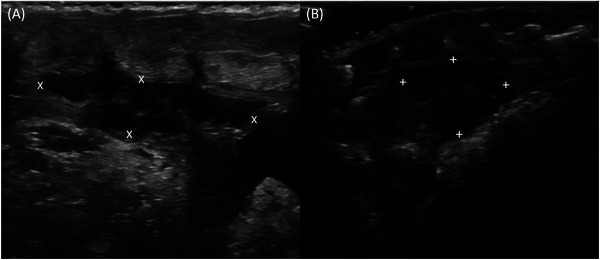

泌尿生殖道的评估在蜥蜴的疾病诊断中具有重要意义,超声检查是最适合的影像学检查方法。然而,对于大多数通常饲养的物种,没有可用的参考数据。这项前瞻性解剖分析研究的目的是超声检查四种最常见的蜥蜴物种的泌尿生殖道,并比较它们的肾脏、睾丸和卵巢。其中包括41种蜥蜴、14种胡须龙、15种豹壁虎、7种面纱变色龙和5种豹变色龙。使用了8-18 MHz曲棍球棒传感器和6-15 MHz线性传感器。记录各器官的矢状面和横切面图像。所有蜥蜴的肾脏、19只蜥蜴中的18只蜥蜴的睾丸和22只蜥蜴中的13只蜥蜴的卵巢都能被观察到。本研究结果可为今后对上述物种的研究提供参考价值。

The assessment of the urogenital tract is of great importance in the diagnosis of diseases in lizards, and sonographic examination is the most suitable imaging method for this purpose. However, reference data are not available for most of the commonly kept species. The objective of this prospective anatomical analytical study was to sonographically examine the urogenital tract of four of the most commonly kept lizard species and compare their kidneys, testes, and ovaries. A total of 41 lizards, 14 bearded dragons (Pogona vitticeps), 15 leopard geckos (Eublepharis macularius), seven veiled chameleons (Chamaeleo calyptratus), and five panther chameleons (Furcifer pardalis) were included. An 8-18 MHz field hockey stick transducer and a 6-15 MHz linear transducer were used. Sagittal and transverse images of the organs were recorded. The kidneys could be visualized and assessed in full length in all lizards, the testes in 18 of 19, and the ovaries in 13 of 22 lizards. The results of the current study could serve as reference values for future studies on the species mentioned.